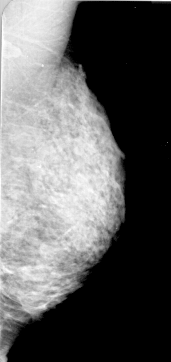

A_1000_1.LEFT_CC

LEFT_CC LINES 4726 PIXELS_PER_LINE 2221 BITS_PER_PIXEL 16 RESOLUTION 42 OVERLAY

FILE: A_1000_1.LEFT_CC.OVERLAY

TOTAL_ABNORMALITIES 1

ABNORMALITY 1

LESION_TYPE CALCIFICATION TYPE PLEOMORPHIC DISTRIBUTION CLUSTERED

ASSESSMENT 4

SUBTLETY 2

PATHOLOGY MALIGNANT

TOTAL_OUTLINES 1

BOUNDARY